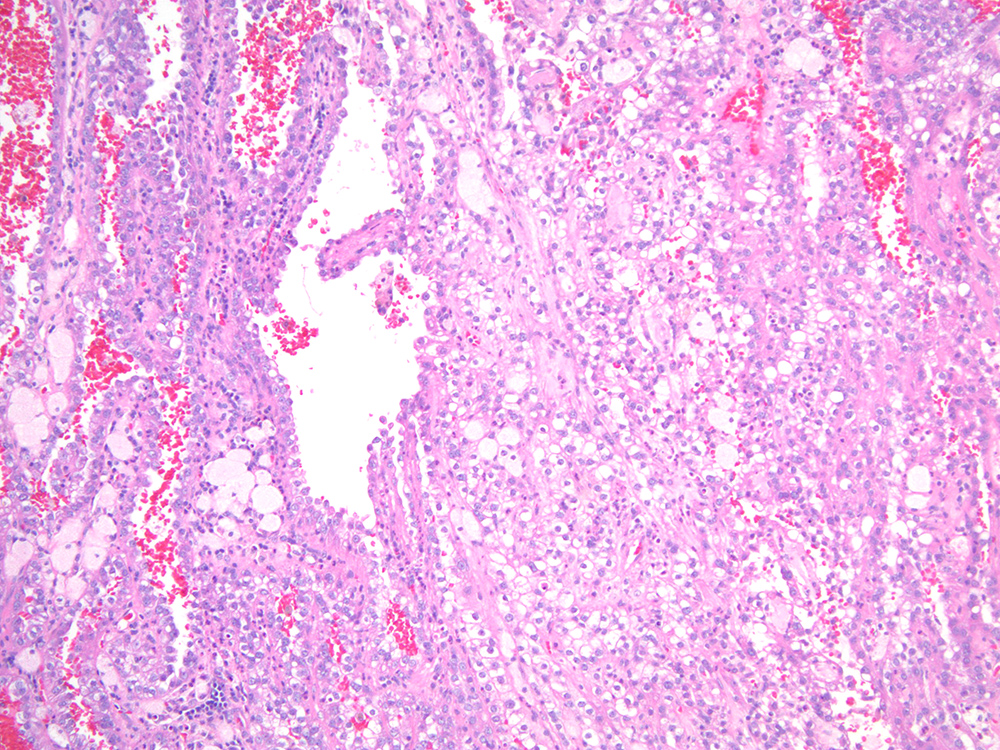

Renal tumor grading

Case ID: 713